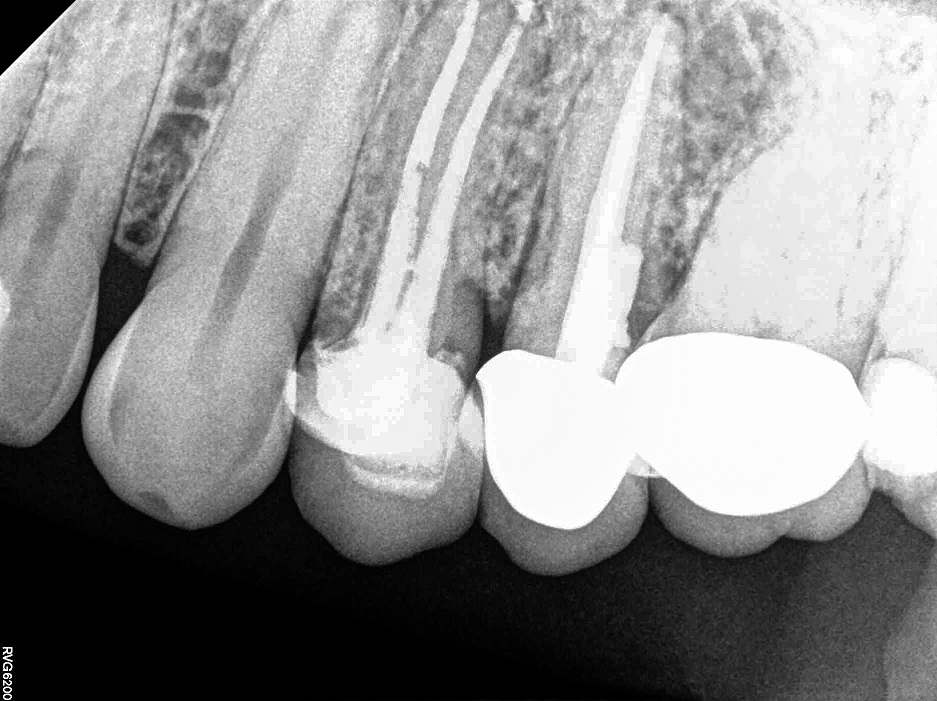

На післяопераційній рентгенограмі видно чудову кінцеву

посадку коронки й штифта (мал. 11).

Фото 11. Післяопераційна рентгенограма.